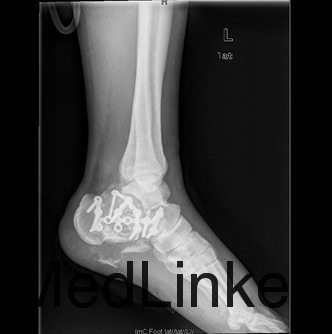

患者男,37岁,因“外伤后双足跟疼痛、肿胀伴腰痛11+天”入院。患者11+天前和工友施工时不慎从二楼摔下,双足跟着地,当时即感双足剧烈疼痛,踝关节活动障碍,伴腰背部疼痛,左足跟长约3厘米伤口,患者诉可见骨断端外露,伤后2小时患者被送往当地人民医院,急诊行清创缝合术,术后给予输液、抗炎、消肿等对症治疗,双足水肿减轻,患者为求诊治进一步诊治来我院,急诊以双足跟骨折收住我科。

查体:双足中度肿胀,左足跟底内侧长约3cm清创缝合术后伤口,伤口干燥,无红肿渗液,双足背、足底、双踝关节中度肿胀,双足皮温正常,足背动脉正常扪及,双下肢肌力五级,双足趾活动正常,双踝关节疼痛活动受限。 辅查:双足X线示:双足跟粉碎性骨折,关节面塌陷。

初步诊断:1、右跟骨粉碎性骨折2、左跟骨粉碎性开放性骨折清创缝合术后 诊疗计划:拟行双侧跟骨切开复位植骨、钢板、螺钉内固定术+髂骨取骨术